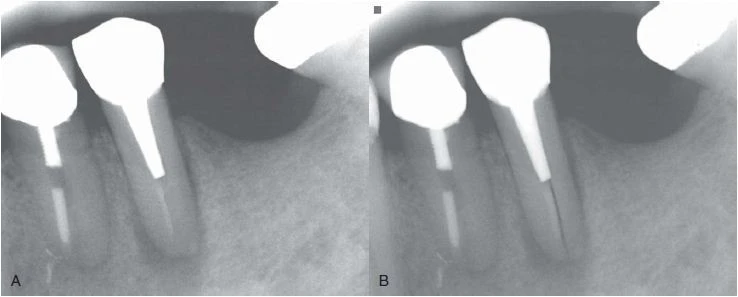

Đường xi măng

Nứt dọc chân răng hoặc chia chân răng có thể mở rộng thừ mặt gần đến mặt xa của răng, thường đường nứt này xảy ra sau khi thực hiện điều trị nội nha. Đôi lúc sẽ thấy một hình ảnh “đường xi măng” dọc hoặc băng ngang qua chân răng. Phần xi măng bị đẩy qua đường nứt, sau đó có thể thấy được trên X quang. Nha sĩ có thể nhầm với hình ảnh phần xi măng bị đẩy qua ống tuỷ phụ, nhưng trong trường hợp nứt răng thì phần xi măng sẽ bị đẩy ra khuêch tán hơn và không có hình ảnh ống tuỷ bên đổ ra từ ống tuỷ chính.

Hình 12. Hình ảnh “đường xi măng”